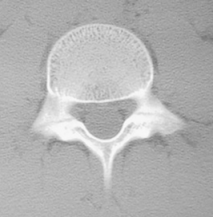

So, I would say that most of the practitioners I know in this field, will, depending on the patient’s history–their sport, their specific triggers for pain, how long they have experienced pain–will order 2 view (standing lateral and AP) lumbar spine or 4 view (additionally a left and right oblique view) plain films. Whether to order a 2 view or 4 view is a controversy in and of itself (next blog post); regardless, the sensitivity of plain radiography is rather low, and often times a clinician will follow up a negative plain film with an MRI, CT scan or SPECT scan to confirm, or rule out, the diagnosis.